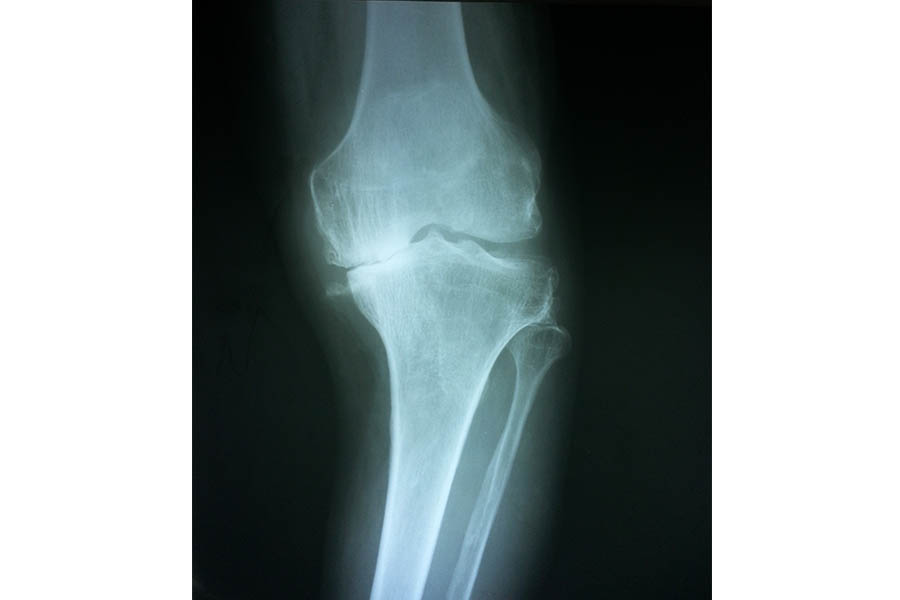

Total Knee Replacement

Case 1